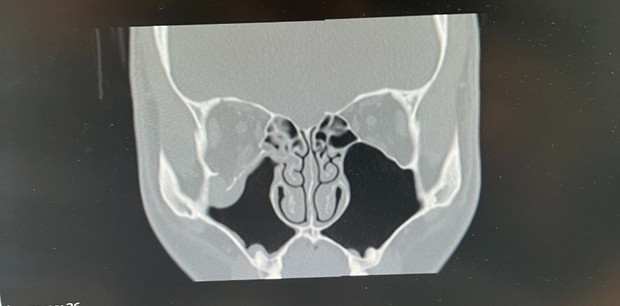

안와골절인데 ct한번만 봐주실 수 있나요?

지금 해외에서 안와골절이 된 상태입니다.

ct를 촬영해봤는데 여기에서 수술할지 한국에서 할지 선택하라고 하더라구요...

당장 수술을 하는게 나을까요?

안한다면 수술안하고 비행기타는건 상관없나요?

그리고 수술을 꼭 해야하는 상황인지 궁금합니다.

안와골절부위로 공기가 드나들 수 있는 상태라면 비행 중 다른 합병증이 발생할 우려가 있습니다. CT 한 컷으로는 이에 대한 평가가 어려우니 의사에게 이 부분을 확인하시는게 좋겠습니다.